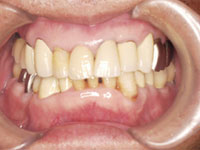

完成後、長いインプラントと短いインプラントを組み合わせきちんと噛めるように調整を行なう。

骨な少なくとも、サイナスリフトという大掛かりな外科手術を行なわずにインプラント治療が実現することができました。